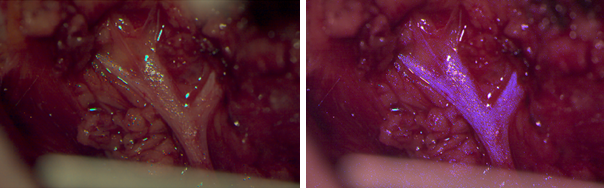

Further, we develop techniquesways to appropriatley visualize the extracted multispectral tissue information in a microscope or endoscope, e.g. by enhancing the reconstructed data in the relevant spectral range (e.g. 460 nm to 480 nm for nerve, see image).

Example for the enhancement of nerve tissue